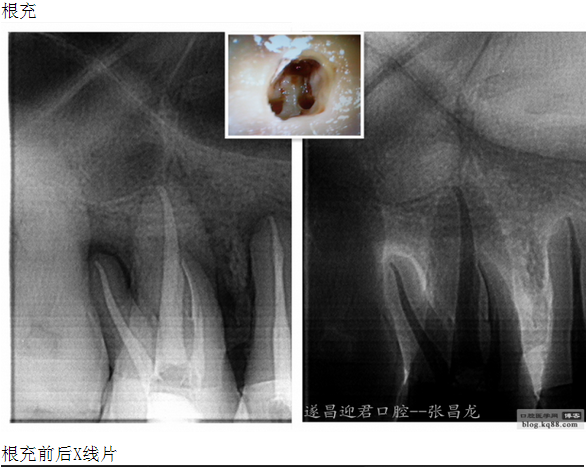

下面是我最近的一個患者,患者14,15,16均因楔狀缺損導(dǎo)致牙髓壞死,根管治療期間,16的近中頰根發(fā)生了斷針。